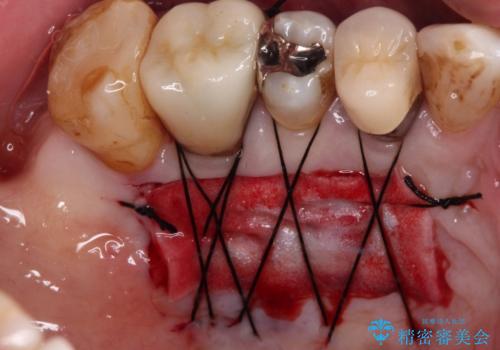

診察したところ、前歯は反対咬合であり、その影響で抜歯が必要な奥歯があることが分かりました。

抜歯が必要な奥歯は、インプラント並びにブリッジにより補綴を行い、上下前歯は反対咬合を改善させるように補綴治療を行うこととしました。

健全な歯を削ってセラミッククラウンに置き換えることは、本来避けるべき治療と考えますが、今回は①患者様が60歳を越えていること、②要改善の咬合により抜歯が必要な奥歯があること、③反対咬合の前歯改善の手段としてセラミック治療が選択肢にあることなどから、全顎的なセラミック治療を行うこととしました。

- 外科手術のため、術後に痛みや腫れ、違和感を伴います

- 外科手術のため、術後に出血、痛みや腫れ、違和感を伴います